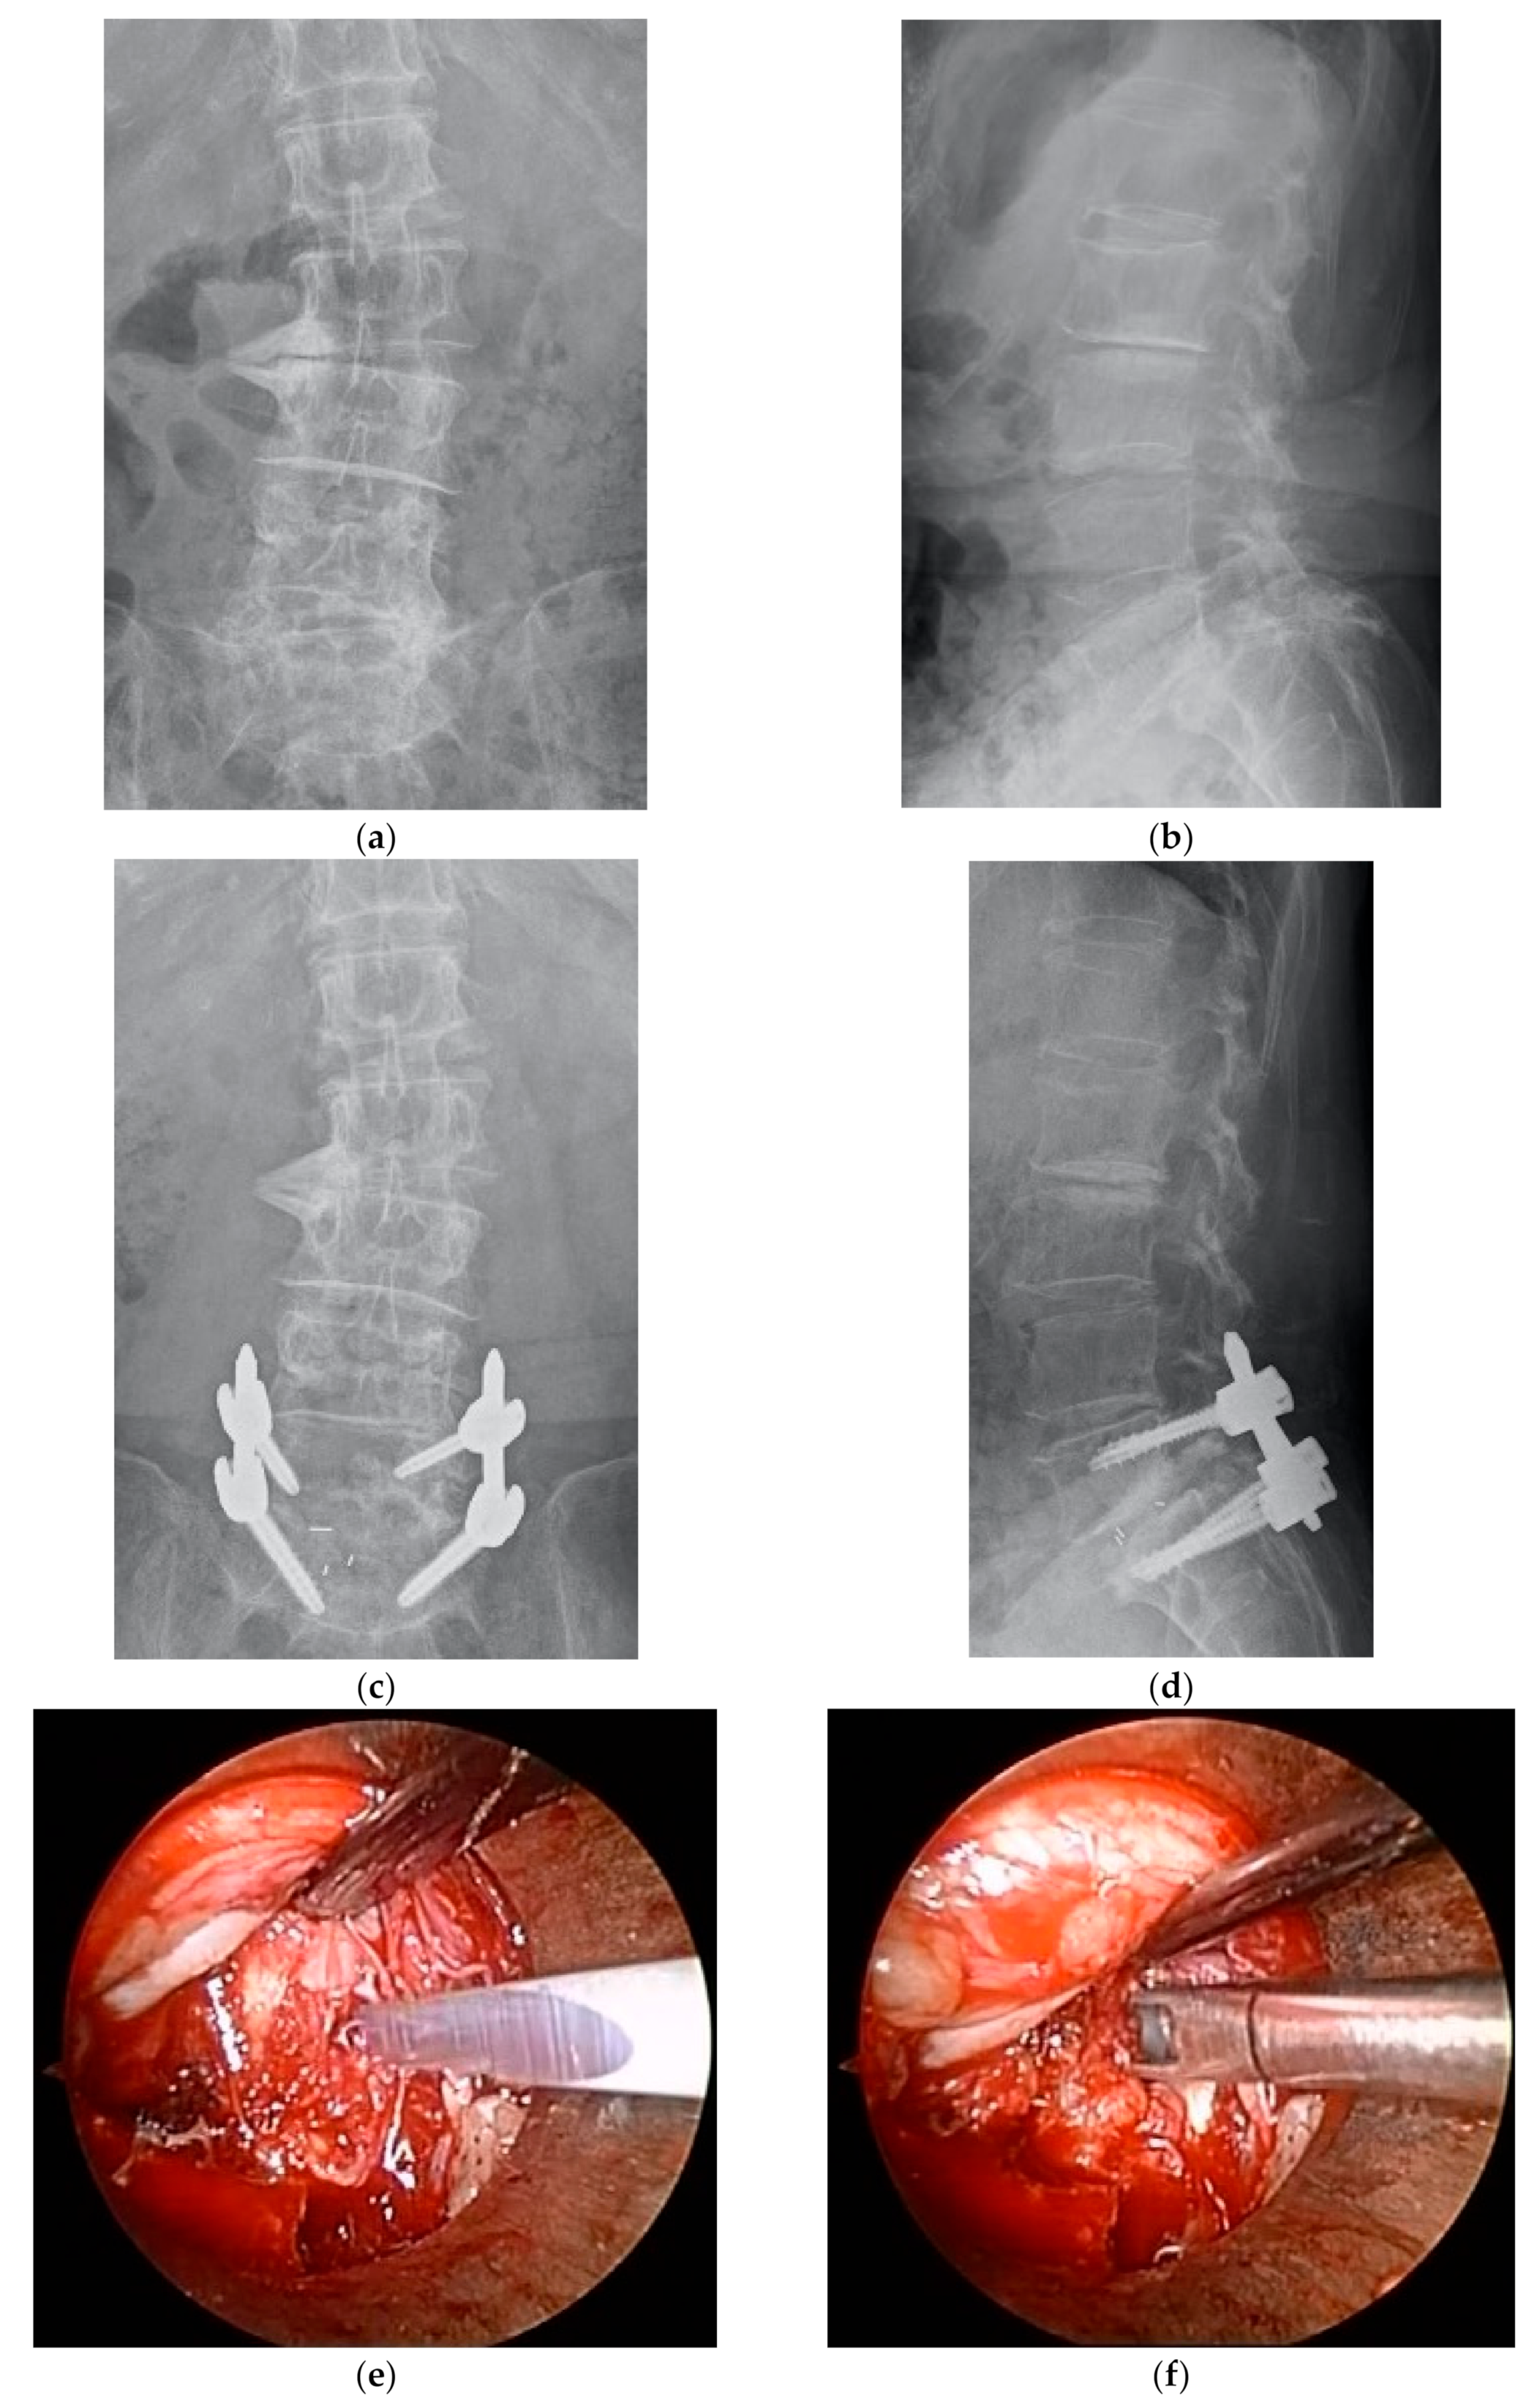

A total of 155 consecutive patients who met the aforementioned inclusion criteria were registered for the study. Six of these patients lacked complete preoperative data; therefore, 149 patients were eligible for analysis. Of these patients, 72 underwent ME-PLIF (ME group), and 77 underwent open PLIF (open group); the specific procedure was determined at each hospital. Two facilities performed ME-PLIF on all patients with the single-level disease, while three facilities performed open PLIF on all patients; at a sixth facility, both procedures were performed. ME-PLIF procedures were performed in accordance with previously reported guidelines [12]. First, a 20 mm incision was made into the skin 15 mm symptomatic outside from the midline on the level of the intervertebral disc. Subsequently, using fluoroscopic guidance, a METRx (18 mm, Medtronic Sofamor Danek., Dublin, Ireland) or ESD II tubular retractor (20 mm, Japan Medical Dynamic Marketing, Inc., Tokyo, Japan) was placed at a site overlying the disk space. All procedures leading to interbody fusion, including decompression, removal of an intervertebral disc, grafting of autologous bone and cage insertion, were performed within the microendoscopic field connected to the tubular retractor. Either a polyetheretherketone (PEEK) or titanium interbody cage filled with autologous bone was inserted. After the microendoscopic procedure, pedicle screws were inserted percutaneously under fluoroscopic guidance. We indicated the perioperative and postoperative radiographs, intraoperative microendoscopic surgical field and postoperative wound in patients who underwent ME-PLIF (Figure 1). The traditional open PLIF was performed via a posterior midline incision. After unilateral or bilateral decompression of the spinal canal, grafting of autologous bone and cage insertion was performed at one or both sides. Pedicle screws were inserted from the same surgical field.

Figure 1.

(a) Preoperative anterior-posterior (AP) radiograph. (b) Preoperative lateral radiograph. (c) Postoperative AP radiograph. (d) Postoperative lateral radiograph. (e) Removal of the intervertebral disc, intraoperative microendoscopic surgical field. (f) Curettement of the intervertebral disc, intraoperative microendoscopic surgical field. (g) Cage insertion, intraoperative microendoscopic surgical field. (h) Postoperative wound.